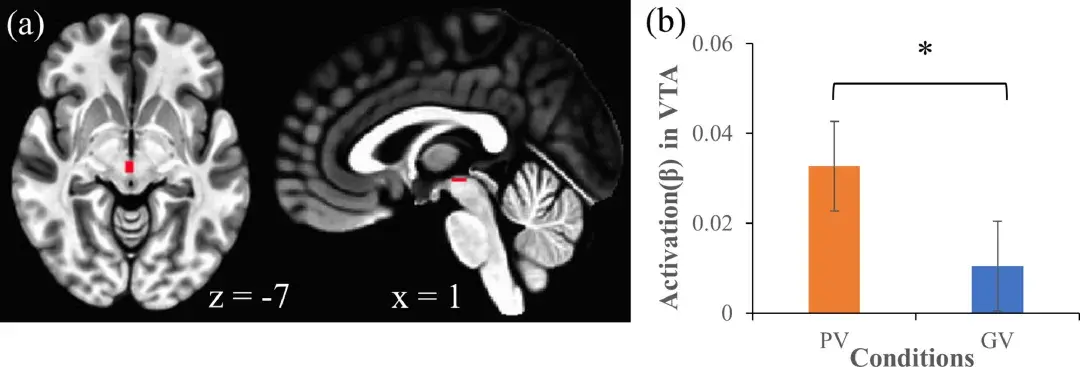

图4 . (a) VTA 的掩模重叠在 MNI模板上。(b) PV 和 GV 条件下 VTA 的差异**达到统计学显着性。* p < 0.05。

表3:PV和GV条件下VTA、NAc和SN的统计结果。注:* p < 0.0056(Bonferroni 校正,p 值 (0.05)/9 检验)。缩写:VTA,腹侧被盖区;NAc,伏隔核;SN,黑质;PV、个性化视频;GV,广义视频。

总之,实验结果表明个性化视频**了与自我参照思维相关的大脑区域,尤其是DMN的某些部分,以及与奖励机制相关的腹侧被盖区。这些区域的“被**”,或许可以解释短视频尤其是“个性化"推荐产生的"上瘾"行为。